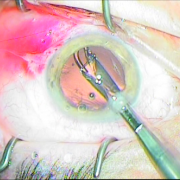

ΙΚ1 ΜΙΚΡΗ ΚΟΡΗ ΛΕΥΚΟΣ ΚΑΤΑΡΡΑΚΤΗΣ ΜΕ ΤΡΑΥΜΑΤΙΚΗ ΡΗΞΗ ΟΠ ΠΕΡΙΦΑΚΙΟΥ ΑΠΟ ΕΓΧΥΣΗ ΑΝΤΙVGEF ΠΑΡΑΓΟΝΤΑ

Μικρή κόρη λευκός

καταρράκτης με τραυματική

ρήξη οπ.περιφάκιου από

έγγχυση ANTIVGEF παράγοντα

ΕΝΘΕΣΗ ΔΙΑΣΤΟΛΕΑ ΙΡΙΔΟΣ

Ένθεση διαστολέα ίριδος

ΧΡΩΣΗ ΠΕΡΙΦΑΚΙΟΥ

Χρώση περιφάκιου

ΚΑΨΟΥΛΟΡΗΞΗ

Καψουλορήξη

ΦΑΚΟΘΡΥΨΙΑ

Φακοθρυψία

ΔΙΑΠΙΣΤΩΝΕΤΑΙ Η ΡΗΞΗ ΤΟΥ ΟΠ.ΠΕΡΙΦΑΚΙΟΥ

Διαπιστώνεται η ρήξη

του οπ. περιφάκιου

ΠΡ.ΥΑΛΟΕΙΔΕΚΤΟΜΗ

Πρ. υαλοειδεκτομή

Ένθεση φακού οπ. θαλάμου